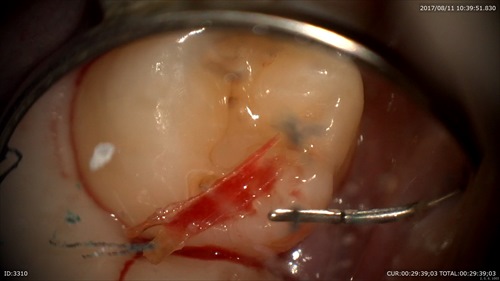

丁寧にデブライドメント

あれっこれはなんだ?歯と歯の間に歯石?

ネギ!!

歯茎の溝(歯周ポケット)が深くなるとこのような物も自分の歯ブラシではとれなくなります。歯周病って怖いですね。